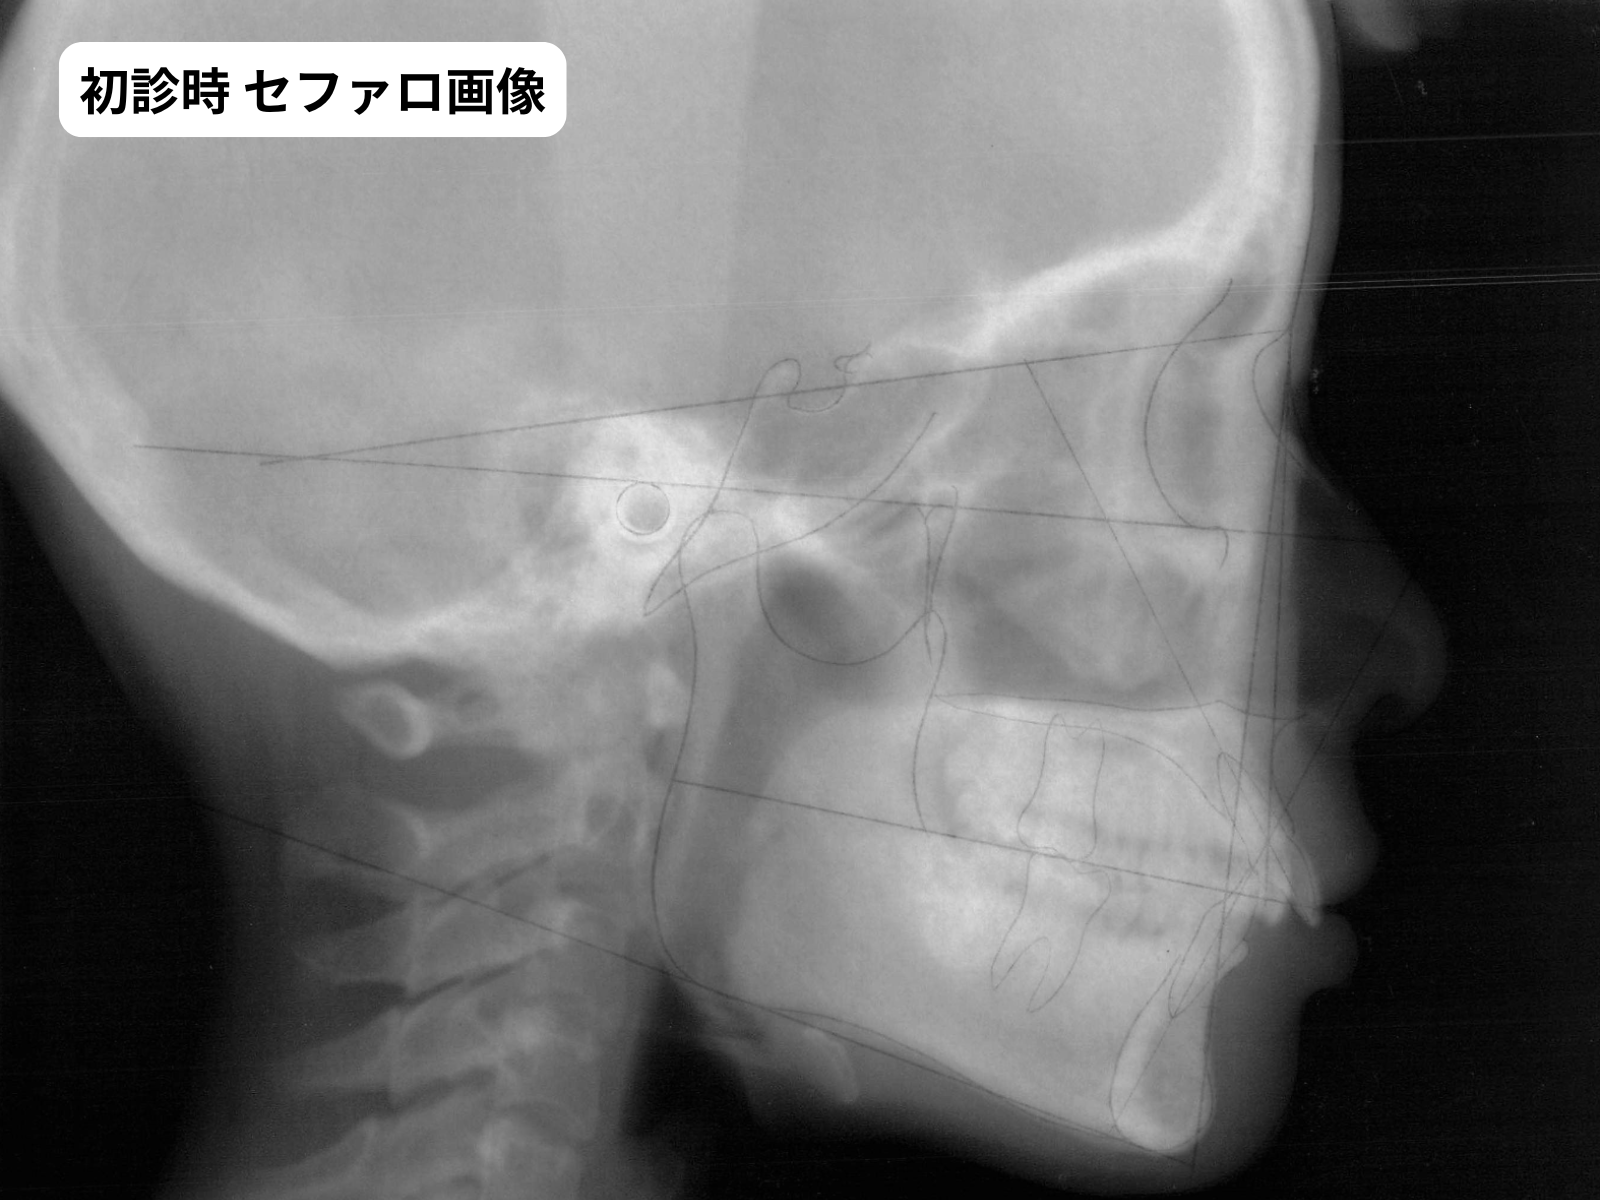

さらに、セファロ分析で骨格を確認したところ「ローアングル傾向」(顔が短く見える骨格パターン)と判定。これは過蓋咬合が悪化しやすく、治療が難しい組み合わせです。

歯槽性であれば歯の移動で対応可能。骨格性が強いと外科治療も視野に入ります。歯槽性か骨格性かは セファロ分析(頭部X線規格写真)でしか正確に判別できません。本症例はセファロトレースで歯槽性と判定し、歯の移動で対応可能と判断しました。

セファロトレース・パノラマX線(治療判断の根拠)

セファロ 初診時セファロトレース|ローアングル骨格判定|奈良の矯正歯科

セファロ分析の数値(治療判断の根拠)

項目 正常範囲 本症例の値 判定

FMA(下顎下縁角)22〜28°16°ローアングル

ANB(上下顎前後差)2〜4°3.5°正常範囲(骨格Class I)

U1 to SN(上前歯傾斜)約105°105°正常範囲

L1 to Mand(下前歯傾斜)約93°92°正常範囲

Overbite(重なり)2〜3mm7mm重度過蓋咬合

U-lip to E-line0〜-2mm+1mm口元バランス概ね保たれている

※ 数値は セファロトレースから算出。ローアングル骨格+重度過蓋咬合だが、口元バランスは保たれていることが数値で確認できました。

5枚法で過蓋咬合の重度さ右下1番の欠損が確認できます。セファロトレースでは、骨格がローアングル傾向であること、過蓋咬合の原因が歯槽性であることが数値で示されました。これらを総合してマウスピース×非抜歯という判断に至りました。